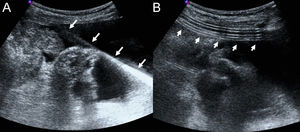

La inserción del catéter se realiza del siguiente modo: tras obtener el consentimiento informado y con el paciente en ayunas se estudia la distribución de la ascitis y se marcan dos puntos en la piel separados unos 7cm en una línea paralela al margen costal inferior, ya que una localización más caudal es incómoda cuando se utiliza cinturón (fig. 2). Se esteriliza la piel y se anestesia con 20cc de mepivacaína al 1% el punto medial, el punto lateral hasta el peritoneo y el trayecto subcutáneo entre ambos. Se accede a la cavidad peritoneal desde el punto lateral con una aguja del calibre 18G y se avanza una guía metálica de punta en J que se deja una vez retirada la aguja. Con un bisturí se abre un ojal de 1cm en sendos puntos de punción, para posteriormente avanzar el tunelizador unido al catéter desde el punto medial al lateral. Posteriormente se retira el tunelizador.

Por último se avanza el introductor pelable 16F por la guía metálica en el punto lateral (fig. 3), se retiran el dilatador y la guía y se avanza con rapidez el catéter a través del introductor pelable.

Una vez introducido el catéter (fig. 3) y comprobada la ausencia de acodaduras se procede a suturar las incisiones y asegurar el catéter con seda.